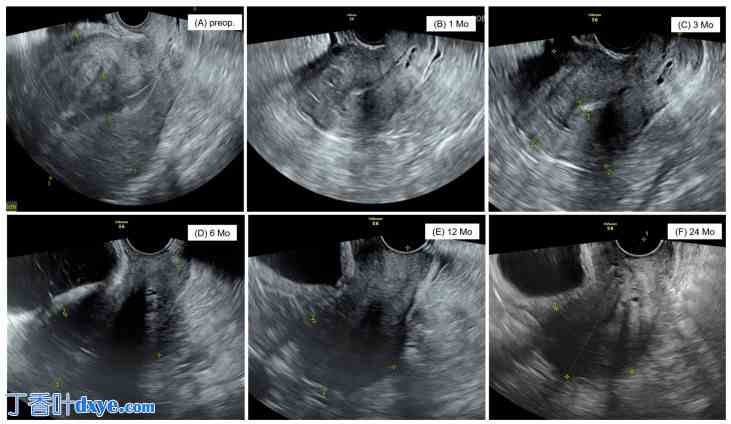

术后连续超声检查显示子宫形态良好,月经过多、痛经等症状以及 CA125 水平显著下降。两年随访期间,未出现子宫增大或临床症状恶化的病例,也未观察到其他手术并发症(图 5)。在子宫腺肌瘤切除术中,术后6个月子宫体积再次增大,术后24个月CA125水平再次升高,其中8例患者出现严重症状,最终需再次手术。这8例患者中,4例行子宫切除术,4例行子宫底切除术。本研究的优势之一在于,它聚焦于一种新的手术技术——单孔腹腔镜下子宫底切除术,这是一种针对无妊娠计划的子宫腺肌症患者的保留子宫手术方法,此前鲜有研究。然而,本研究也存在一些局限性。首先,本研究为单中心回顾性研究,这是一个显著的局限性。其次,样本量不足以推广作者的研究结果。第三,本研究未明确子宫腺肌症的类型、范围和部位。作者认为这些局限性是未来开展多中心前瞻性研究的改进方向。

图 5.

单孔腹腔镜下子宫底切除术后患者的子宫超声图像。(A) 术前,(B) 术后 1 个月,(C) 术后 3 个月,(D) 术后 6 个月,(E) 术后 12 个月,(F) 术后 24 个月。